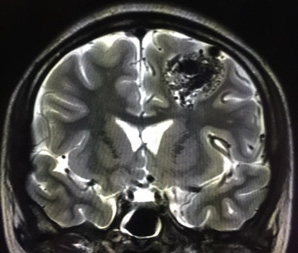

脳動静脈奇形とは、脳にできた異常な血管のかたまり(ナイダス)のことをいいます。通常、脳を栄養する血液は、動脈→毛細血管→静脈の順に流れ、毛細血管から脳へ栄養や酸素を送っています。これに対して、脳動静脈奇形は脳内の動脈と静脈が血管のかたまりであるナイダスで直接つながっており、この中を大量の血液が勢いよく流れています。

脳動静脈奇形が破れると脳出血やくも膜下出血を起こします。また、けいれん発作や頭痛などを引き起こすこともあります。脳動静脈奇形周囲の脳血流不全から認知症状などを呈することもあります。